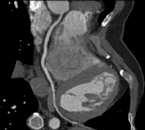

心臓CT

心臓CTでは、心電図により心臓の動きを捉え、造影剤を用いて主に心臓の血管(冠動脈)の形態や石灰化の有無などを診る検査です。

心臓カテーテル検査に比べて侵襲性が低く、検査にかかる時間も短いことから患者様の負担が小さいのが特徴です。

検査の際に、20秒程度の息止めをしていただきます。息止めが不十分な場合、画像が不明瞭となり血管の評価が困難なことがございます。ご協力お願いします。

また、不整脈の多い方では画像が不明瞭となり評価が困難なことがあります。